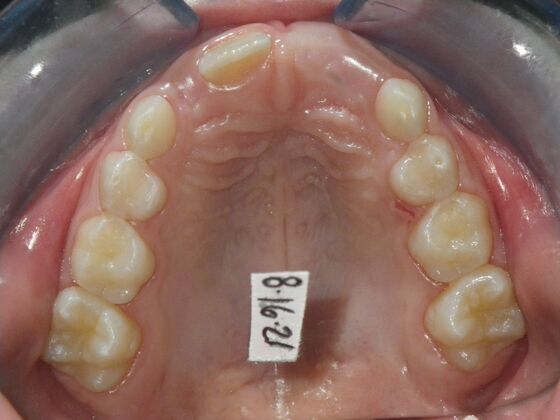

Patient presents with delayed eruption of the upper right central incisor and lower anterior crowding. Treatment plan to include exposure of right central incisor with bracket placement and correction of lower anterior crowding.